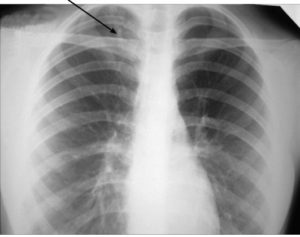

Снимки легких при туберкулезе

С момента открытия рентгеновских лучей (рентгеновских лучей) он активно внедряется во все области медицины, и фтизиология не является исключением. Поскольку легкие у больных туберкулезом имеют отличительные особенности, радиологические методы стали применяться для диагностики, наблюдения за динамикой процесса и профилактики. Перечень визуализационных методов исследования Для диагностики туберкулеза используются следующие анализы: флюорография; Рентгеновская радиография; компьютерная томография (КТ). …